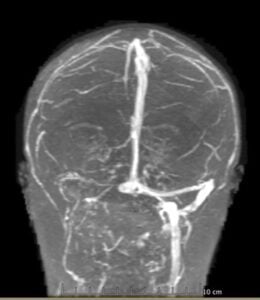

In mid-July, an MRV finally revealed the truth: a clot in my right transverse and sigmoid sinuses. I was rushed to the neuro ICU, where I spent 10 days on a heparin drip. Now I’m on lifelong blood thinners, plus medication to keep the pressure in my head under control, while we wait for the clot to resolve. I’ll also be working with a specialist to better manage my essential thrombocythemia.

Looking back, we realized the clot was visible on my June MRI but was missed, delaying my diagnosis by more than six weeks. This entire experience has turned my world upside down, but I’m so grateful to still be here. The future feels uncertain, but I’ve learned that I’m stronger than I ever imagined, and that by trusting myself and speaking up, I saved my own life.